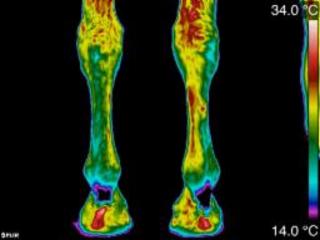

A human touch cannot identify changes in temperature of less than 2-3 degrees, however, a thermal camera can “see” and detect changes of 0.1 degree, making it easy to identify problem areas where heat is not obvious to the touch. Not only can it tell us areas of increased (abnormal) heat but importantly, areas of increased (abnormal) cool. When 'feeling' horses legs for heat it is assumed the warmer leg is abnormal, however thermal imaging can show us that the warmer leg is normal it is in fact the cooler leg that is showing us an abnormal pattern. Thermography should not be seen as a diagnostic tool but as an indicator of the 'where', it is complementary to other imaging techniques such as radiology and ultrasonography, which can then show the 'what'.

| | Injury Prevention If injury could be detected early enough progression to a more serious injury can be avoided. Dr Turner's research has shown that tendon injury can be seen up to as much as 2-3 weeks before clinical signs. |